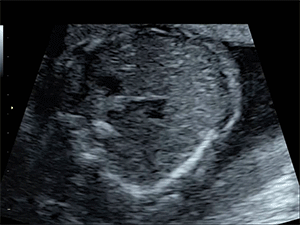

Fig 2a. Ultrasound videos of a normal heart.